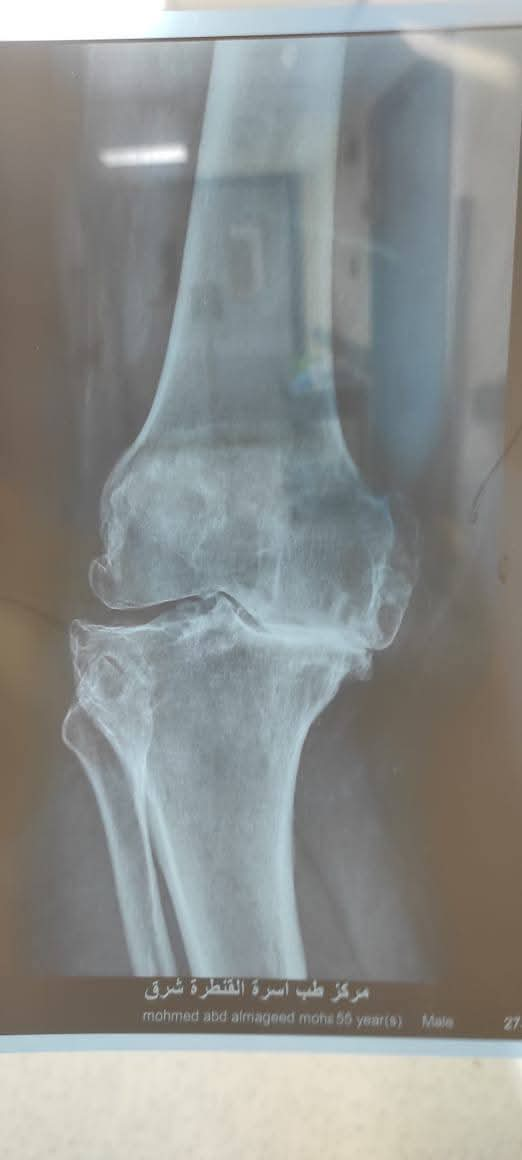

حقق الفريق الطبي بمستشفى القنطرة شرق التابعة لفرع الهيئة العامة للرعاية الصحية في محافظة الإسماعيلية، إنجازًا جديدًا بإجراء عملية دقيقة لاستعدال الركبة وتركيب مفصل ركبة كامل أسمنتي ذي جذع طويل (Long Stem) لمريض يبلغ من العمر 56 عامًا، بعد معاناة طويلة من خشونة متورمة وتشوه شديد بالخارج للركبة اليسرى، وهي من الحالات المتقدمة التي تتطلب مهارة عالية وخطة جراحية دقيقة.

وكان مريض في الستينات من عمره حضر إلى مستشفى القنطرة شرق، وهو يعانى من خشونة متورمة بالركبة اليسرى مع تشوه شديد.

وخلال الجراحة، نجح الفريق في استعدال المحور التشريحي للساق وتصحيح التقوس، ثم تركيب المفصل الصناعي المزود بجذع طويل لضمان الثبات والدعم في الحالات المتقدمة.